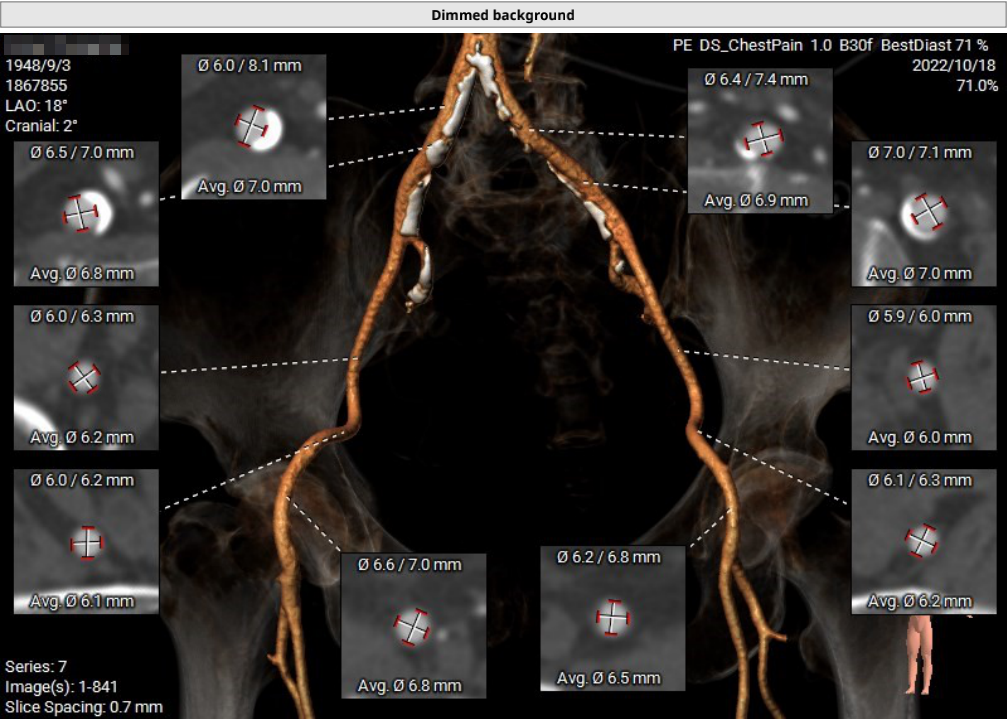

主动脉根部CTA

瓣环周长67.3mm,平均径21.4mm,LVOT周长73.0mm,平均径23.2mm;横位心76°,瓣叶交界钙化粘连;股动脉入路迂曲,分叉高度可,髂总-腹主钙化斑块;左侧血管平均最小内径6.0mm, 右侧血管平均最小内径6.1mm;左、右冠开口高度低,瓣叶长,窦宽相对瓣膜小,冠脉风险高。